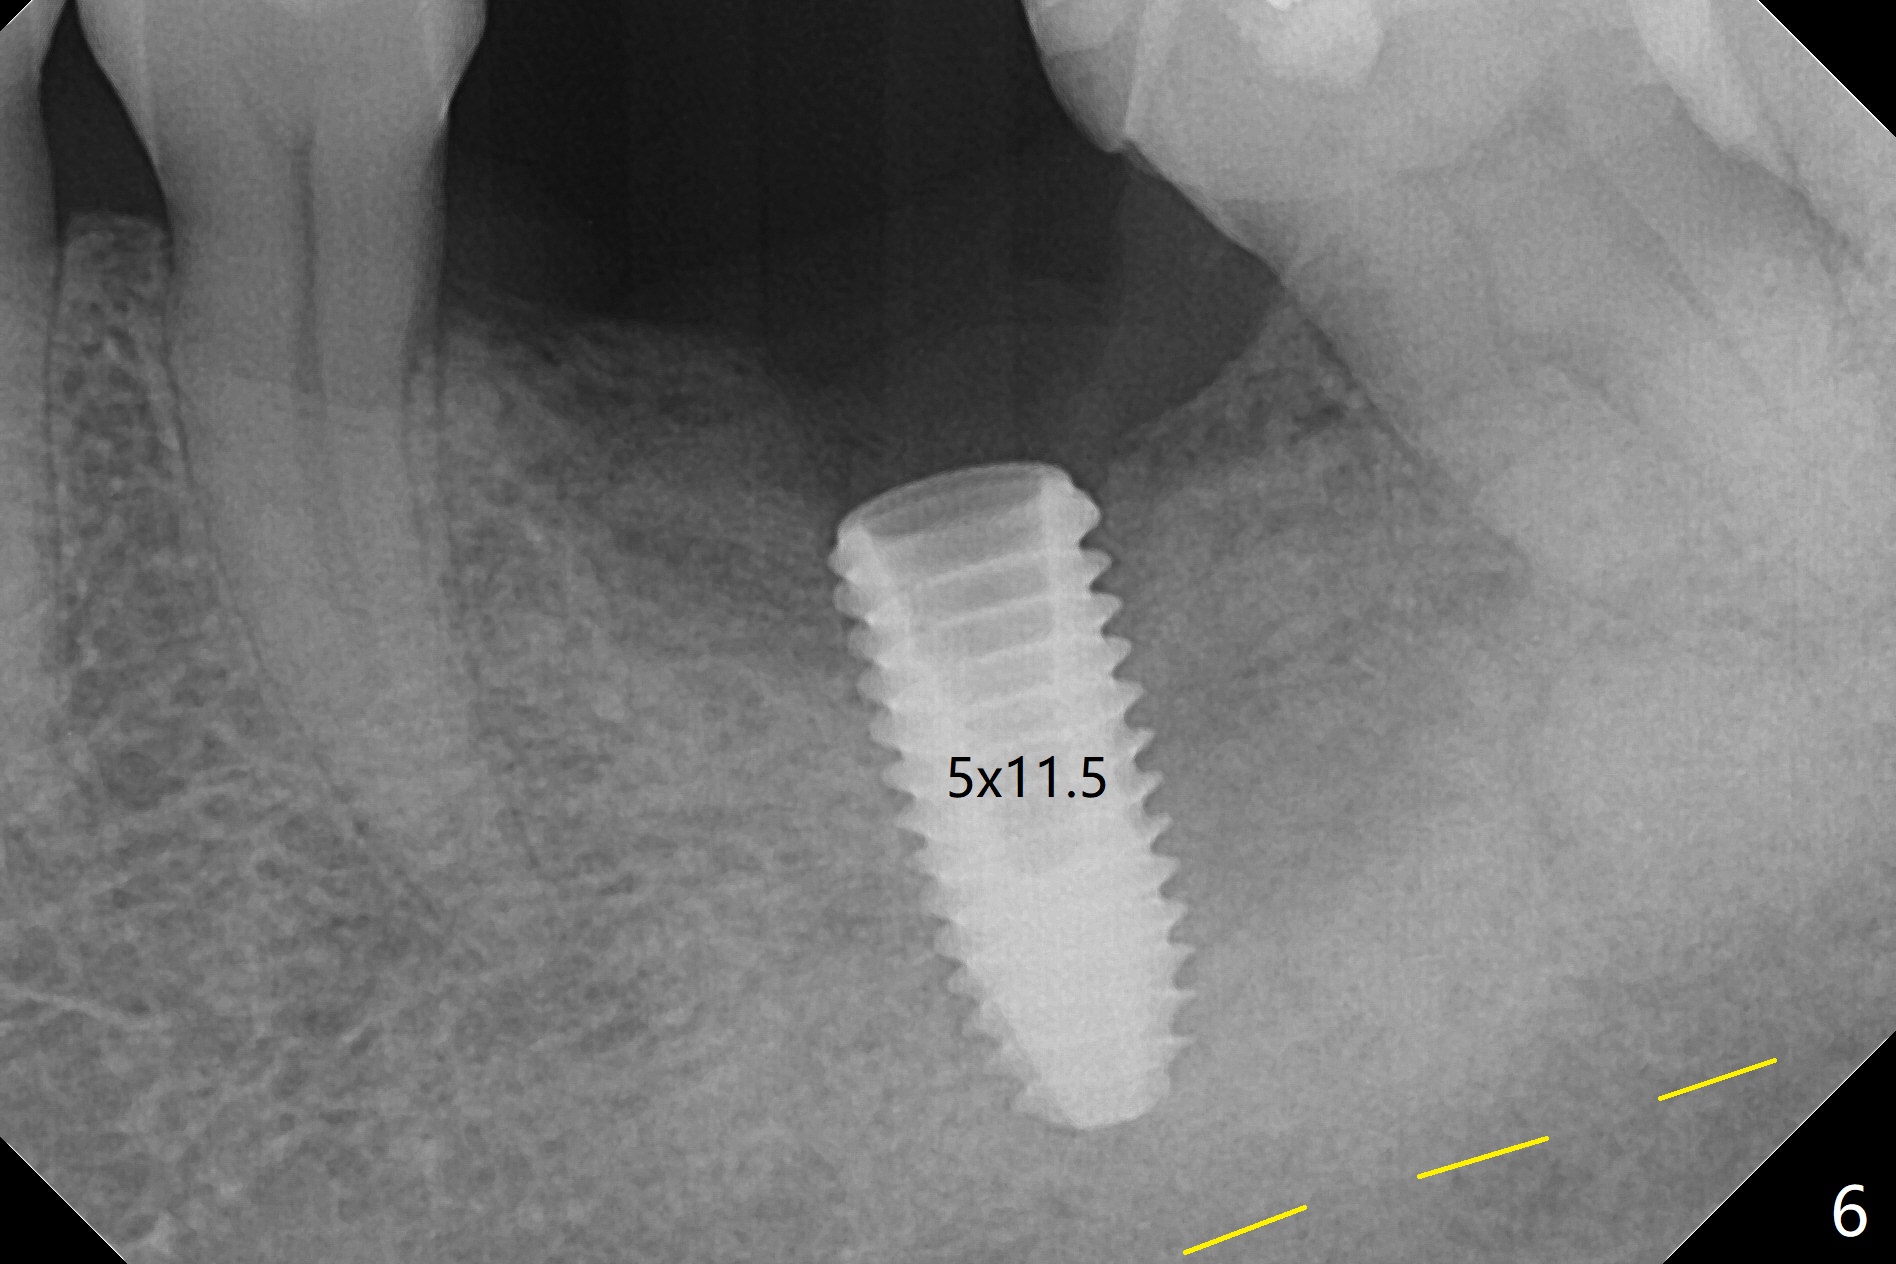

CT taken 4-5 months post extraction shows the outline of the socket at #19 (Fig.1 pink and red dashed line). By the time of surgery (6-7 months post extraction), the ridge looks narrow (Fig.2). In fact the socket does not heal (Fig.3). Osteotomy starts at the mesial border of the socket (Fig.4). When a 5x10 mm dummy implant is placed, the axis begins to be tilted distally (Fig.5 red line), which is more obvious when a definitive longer implant (5x11.5 mm) is placed (Fig.6,7). Osteotomy (Fig.1 arrow) at the mesial slope of the socket (red dashed line) should be initiated more mesial to compensate for the distal drifting while osteotomy is being increased and the implant is being placed. The distal defect is filled with Vanilla graft. Probably due to the mesial slope and the distal defect, the primary stability is <10 Ncm. A healing screw is placed with Vanilla allograft/autogenous bone. The bone forms coronal to the implant 4 months postop (Fig.8 *), which is removed for uncover. The mesial gingival embrasure of the permanent crown is large (Fig.9 *), as related to the mesial undercut associated with a 5.7x4 mm A 15 degree angled abutment (Fig.10). Reduction in the undercut should be able to help lab decrease the gingival embrasure (Fig.11 red line). The bone density around the implant increases with distinct trabecular pattern consistent with stress 5 months post cementation (1 year postop, Fig.12).